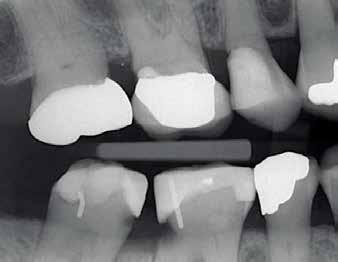

See the bitewing in this image of an existing patient in our practice. Missing #30 causes supra-eruption of #2 with mesial drifting, along with mesial and distal drifting of #31 and #29, respectively.

Also, what happened to #3?

In this case alone, missing one tooth has caused the shifting of three other teeth, in addition to possibly causing the loss of a fourth tooth (#3).